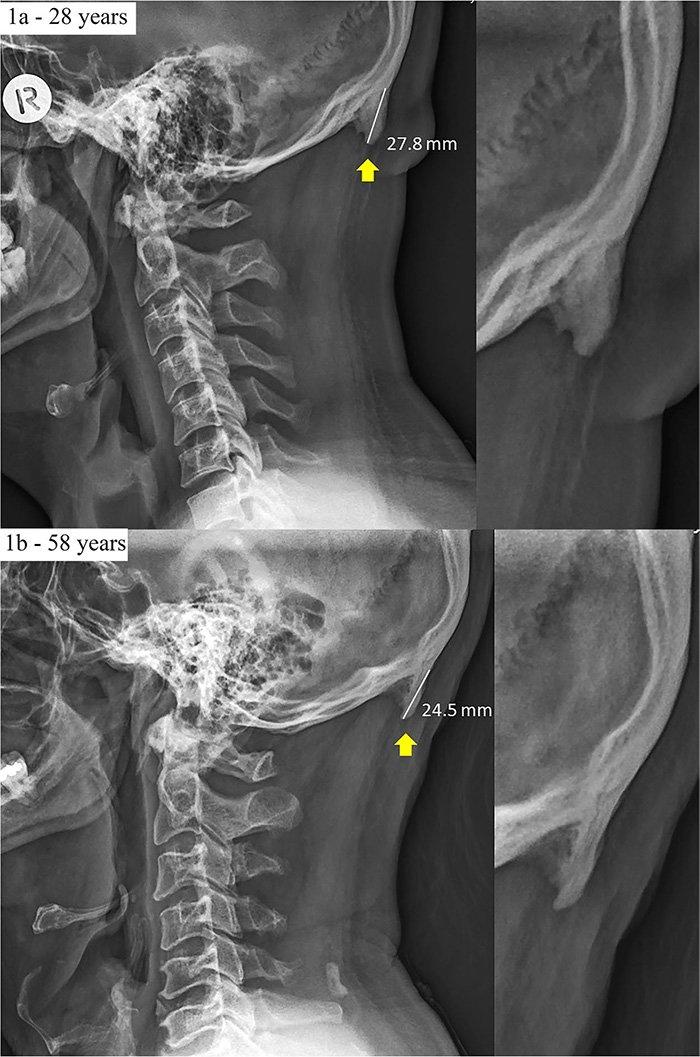

豪サンシャインコースト大学のデビッド・シャハル博士らの研究チームは、18歳から30歳までの若者218名を対象に外側頸部のレントゲン写真を分析し、2016年3月22日、学術雑誌「ジャーナル・オブ・アナトミー」でその成果を発表した。

これによると、被験者のうちの41%に外後頭隆起の突出が認められ、10%は20ミリ以上の外後頭隆起が認められた。外後頭隆起の突出は、女性よりも男性に多く認められ、中には、その大きさが35.7ミリに達するものもあった。なお、ヒトの外後頭隆起は通常5ミリ程度で、10ミリを超えると大きいとされている。

さらに、シャハル博士らの研究チームは、18歳から86歳までの1200名を対象に、年齢や性別、前かがみ姿勢の角度と外後頭隆起の突出との関連についても分析した。科学誌「サイエンティフィック・リポーツ」で2018年に掲載された研究論文によると、被験者のうち33%に外後頭隆起の突出が認められ、男性のほうが外後頭隆起の突出が多く、前かがみ姿勢の角度が大きいほど、外後頭隆起の突出が起こりやすいこともわかった。また、仮説に反して、年齢が高くなるほど、外後頭隆起の突出が起こりにくいことも示されている。